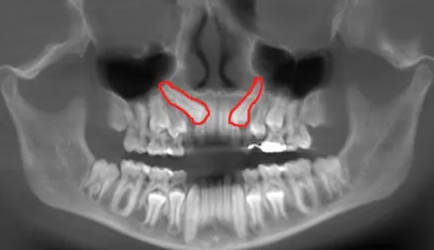

Compensa cuando el diente retenido —habitualmente el canino superior— tiene potencial eruptivo y una posición razonable. En esos casos, abrir una pequeña “ventana” y guiarlo con ortodoncia nos permite evitar extracción y prótesis, integrando tu propio diente en la arcada. Es una solución conservadora que, bien indicada, ofrece resultados muy estables.

Estrategia

Decidimos entre ventana cerrada o abierta según la altura y el grosor de la encía. Adhesivamos un pequeño elemento de tracción (botón o cadena) y aplicamos fuerzas ligeras y continuas coordinadas con el ortodoncista. Cuidamos especialmente los tejidos en zonas estéticas para minimizar la recesión y mantener unas papilas sanas y simétricas.

Riesgos controlables

Monitorizamos la posible anquilosis del diente incluido y la reabsorción radicular de piezas vecinas con revisiones clínicas y radiográficas. El objetivo es un movimiento fisiológico, lento y seguro. Si algo no progresa como esperamos, ajustamos fuerzas o redefinimos la trayectoria de tracción para proteger el tejido y el pronóstico.